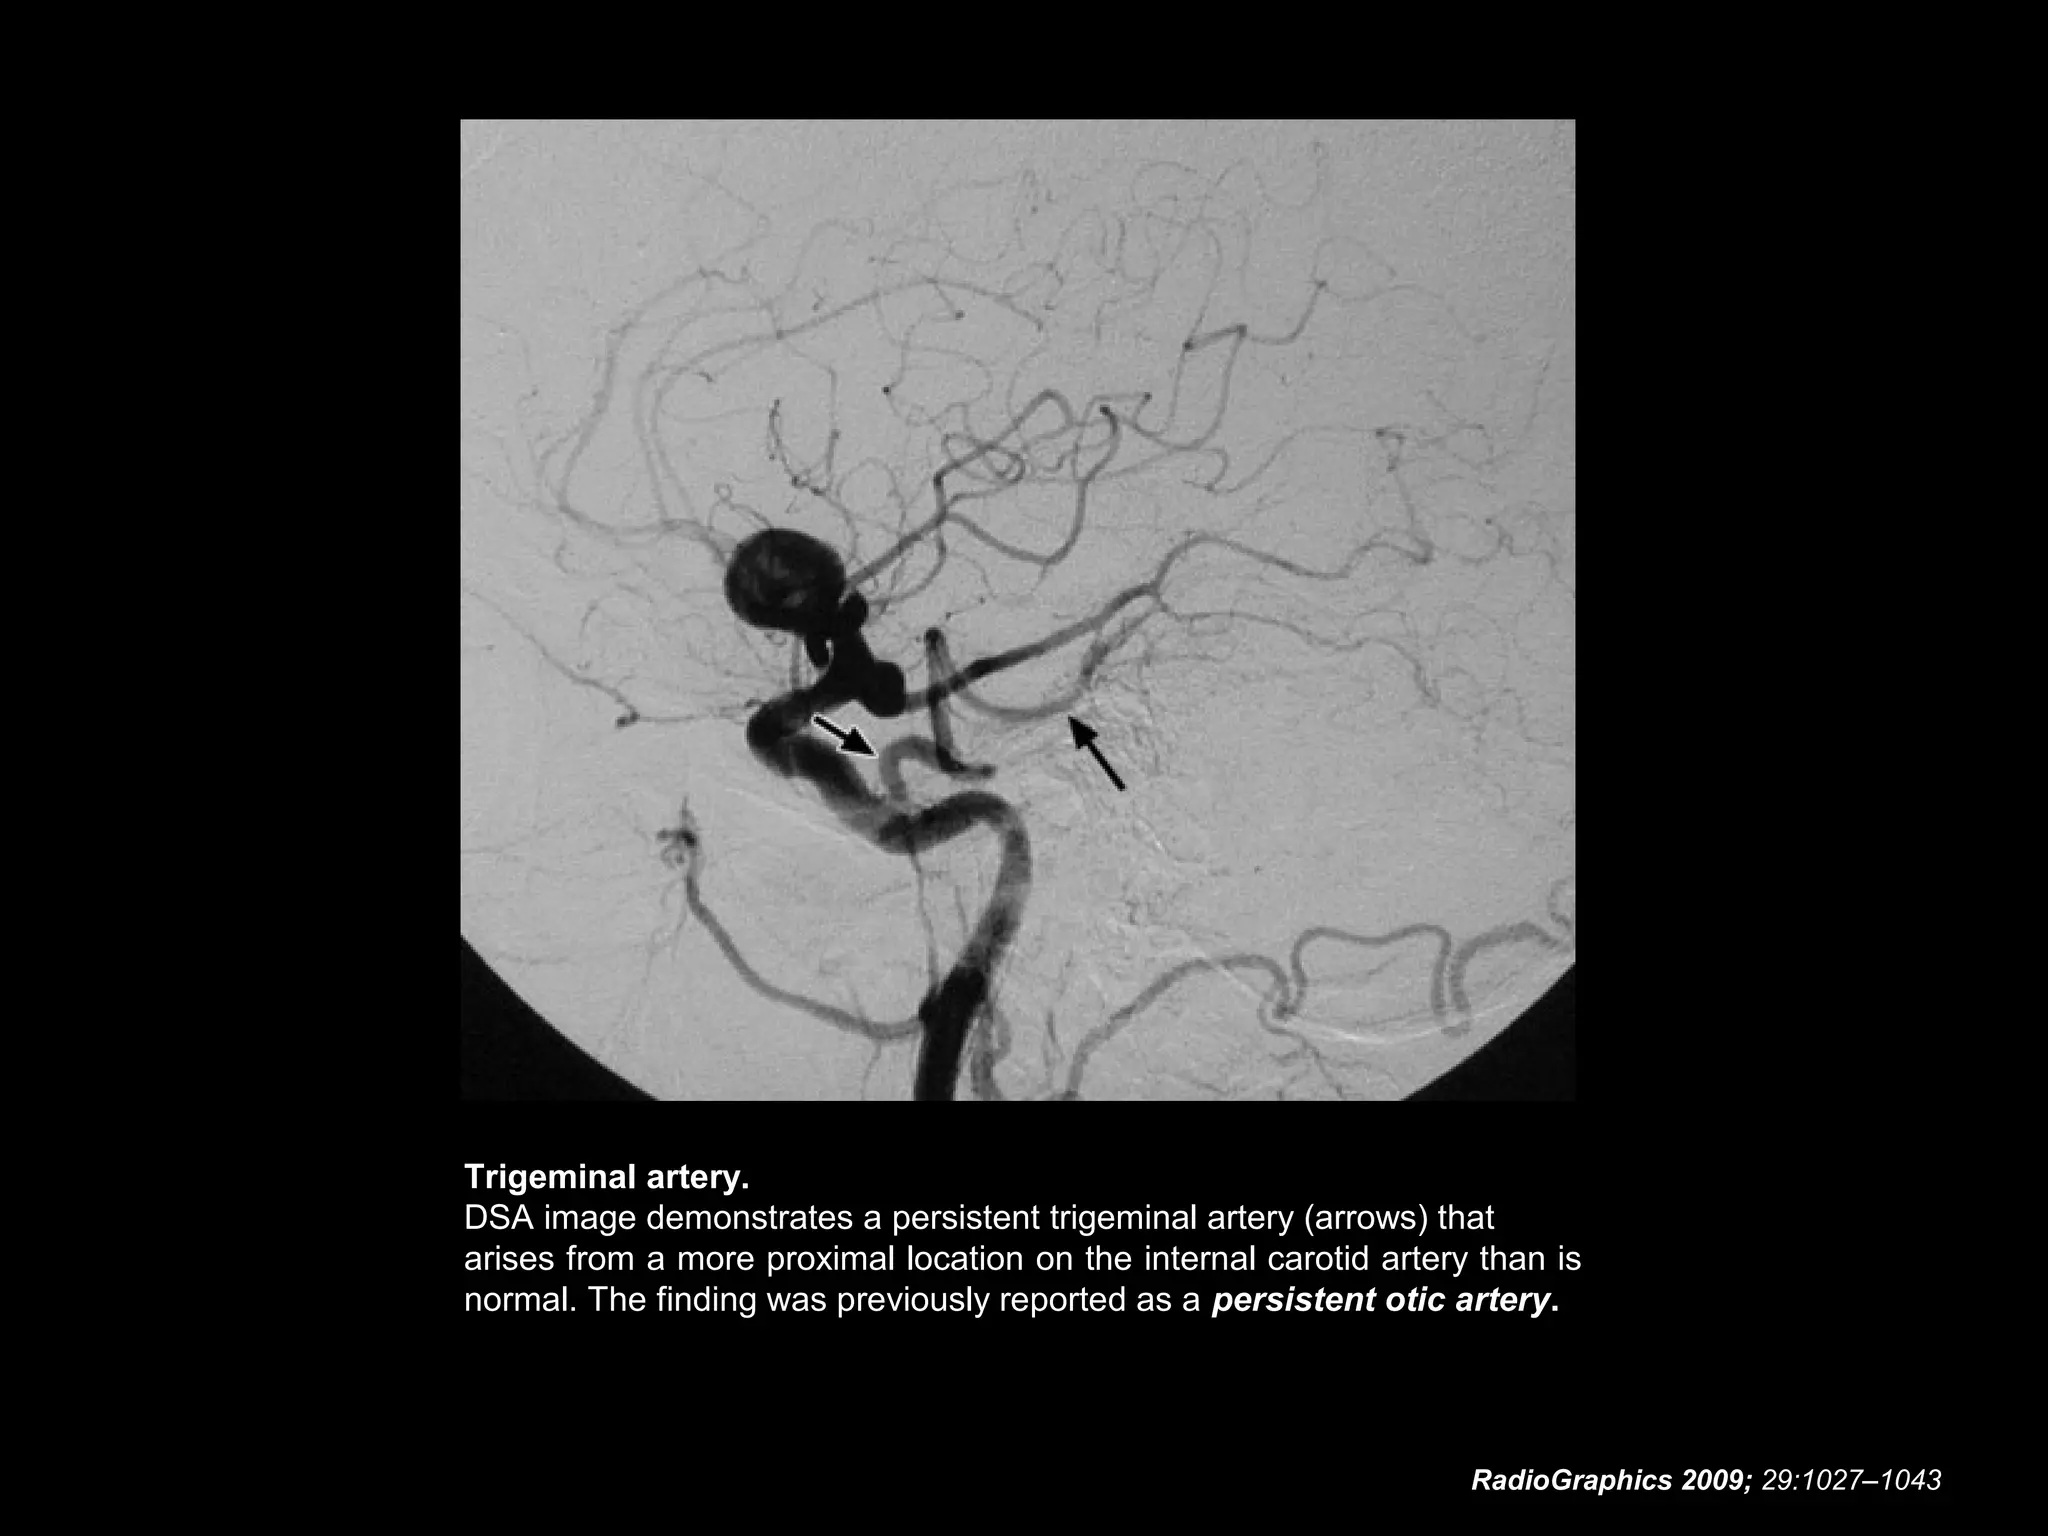

Persistent Otic Artery

• The existence of an otic artery is a matter of controversy.

• Unlike the three embryonic vessels described earlier, an

otic artery has never been identified in lower animals.

• Nevertheless, the medical literature contains descriptions

of such an artery arising from the petrous internal carotid

artery within the carotid canal, coursing laterally through

the internal auditory canal, and anastomosing with the

proximal basilar artery.

• There are eight previous case reports of persistent otic

artery and one of an otic artery variant .

• However, an assessment of the origin, course, and

termination of these reported otic arteries is difficult

because of the variable quality of image reproduction,

the inclusion of only a single angiographic projection, or

both.

RadioGraphics 2009; 29:1027–1043

• Some reported cases of persistent otic artery

may in fact represent a persistent trigeminal

artery.

• Similarly, anastomoses may occur between the

internal auditory artery (a branch of the anterior

inferior cerebellar artery and, thus, the basilar

artery) and the internal carotid artery via

trigeminal and stapedial artery remnants.

• Such anastomoses may be best understood as

representing overlapping vascular territories

rather than persistence of an embryonic vessel.

Trigeminal artery.

DSA image demonstrates a persistent trigeminal artery (arrows) that

arises from a more proximal location on the internal carotid artery than is

normal. The finding was previously reported as a persistent otic artery.

Persistent Otic Artery •The existence of an otic artery is a matter of controversy. • Unlike the three embryonic vessels described earlier, an otic artery has never been identified in lower animals. • Nevertheless, the medical literature contains descriptions of such an artery arising from the petrous internal carotid artery within the carotid canal, coursing laterally through the internal auditory canal, and anastomosing with the proximal basilar artery. • There are eight previous case reports of persistent otic artery and one of an otic artery variant . • However, an assessment of the origin, course, and termination of these reported otic arteries is difficult because of the variable quality of image reproduction, the inclusion of only a single angiographic projection, or both. RadioGraphics 2009; 29:1027–1043

• 81.

Persistent Otic Artery •Some reported cases of persistent otic artery may in fact represent a persistent trigeminal artery. • Similarly, anastomoses may occur between the internal auditory artery (a branch of the anterior inferior cerebellar artery and, thus, the basilar artery) and the internal carotid artery via trigeminal and stapedial artery remnants. • Such anastomoses may be best understood as representing overlapping vascular territories rather than persistence of an embryonic vessel. RadioGraphics 2009; 29:1027–1043

• 82.

Trigeminal artery. DSA imagedemonstrates a persistent trigeminal artery (arrows) that arises from a more proximal location on the internal carotid artery than is normal. The finding was previously reported as a persistent otic artery. RadioGraphics 2009; 29:1027–1043